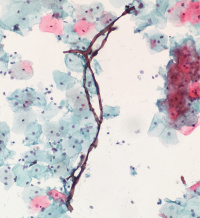

什么东东,难道也是真菌的一种?

• hzh666:  链格孢菌的菌丝,是丝状真菌。分节,褐色是其特点。

链格孢菌之分生孢子及分隔菌丝(箭头示)